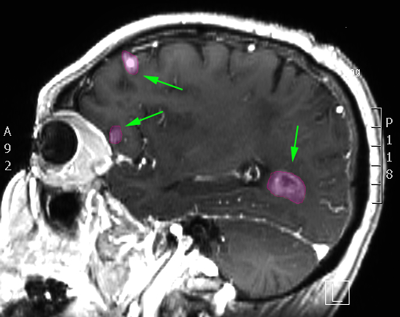

Πολλαπλές μεταστάσεις σε διάφορα σημεία του εγκεφάλου. |